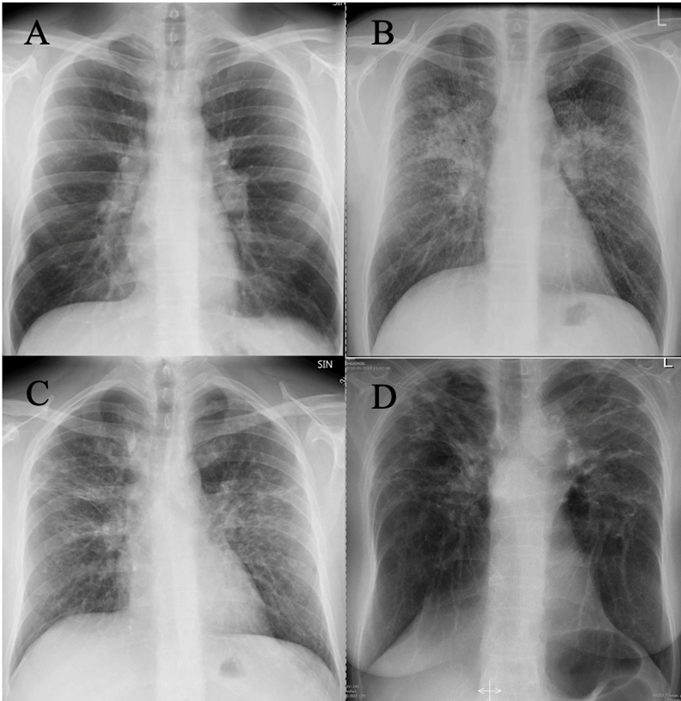

Radiologisk kan pulmonal sarkoidose inddeles i 5 stadier.

| Stadie | Fund | % på diagnosetidspunkt | % Regression indenfor 5 år |

| Stadium 0 | Normalt røntgen af thorax. | 5-15 | |

| Stadium I | Bilateral forstørrelse af lymfeknuder i lungehilus uden lungeinfiltrater.

|

25-65 | 60-90 |

| Stadium II | Forstørrede lymfeknuder i lungehili/mediastinum med lungeinfiltrater. | 20-40 | 40-70 |

| Stadium III | Lungeinfiltrater uden hilusadenitis og uden tegn til fibrose.

10-15 | 10-20 |

| Stadium IV | Lungeinfiltrater med fibrose og skrumpning.

5 | 0 |

Tabel 1: Radiologisk stadieinddeling ved sarkoidose

Figur 3: Røntgen af thorax med sarkoidose i forskellige stadier. A) stadium I, B) stadium II, C) stadium III og D) Stadium IV.

CT/HRCT af thorax kan vise forstørrede hilære og mediastinale lymfeknuder evt. med forkalkninger samt veldefinerede noduli med perilymfatisk distribution samt konsolidering og evt. fibrose typisk med midt- og overzone involvering. CT kan undlades hos patienter med Løfgrens syndrom.